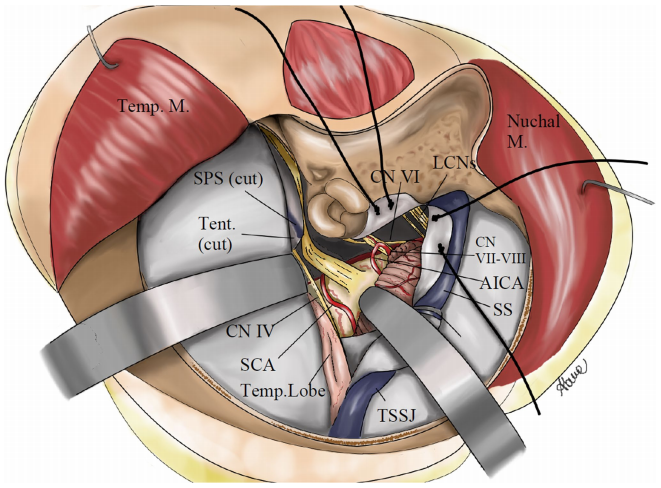

這是福教授對于聯(lián)合巖骨入路的一種微創(chuàng)改良方法。它主要關(guān)注由橫竇乙狀竇交界(TSSJ)在橫竇和蛛網(wǎng)膜下隙(SPS)切斷后移位形成的竇硬膜角和顳小腦間隙。盡管由于肌肉分離較少和顱骨切開術(shù)較小,微型經(jīng)巖骨聯(lián)合入路手術(shù)自由度有所減少,但在巖斜區(qū)和腦干暴露區(qū)域方面,與聯(lián)合巖骨入路幾乎沒有區(qū)別。

手術(shù)通道示意圖:右側(cè)微聯(lián)合巖骨入路(mini-CTPA)

微型經(jīng)巖骨聯(lián)合入路的主要優(yōu)勢在于其微創(chuàng)特性

通過其更小的針對巖嵴和顳小腦走廊的顱骨切開術(shù),可減少手術(shù)對軟組織的創(chuàng)傷,縮短手術(shù)時長,降低手術(shù)風(fēng)險。